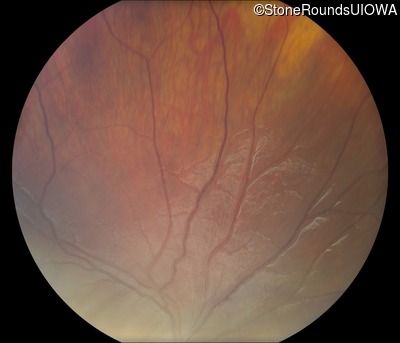

Visit at age: 11 years

Fundus Photography - Right - 20/63 -2

Exemplar